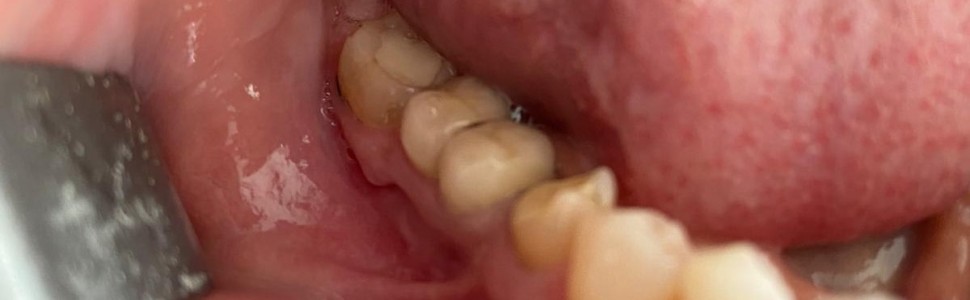

W artykule opisano leczenie periimplantitis przy użyciu lasera erbowo‑yagowego. Zobrazowano w nim skuteczny sposób pozbycia się zapalenia okołowszczepowego implantu, metodę usunięcia ziarniny z powierzchni implantu bez jej uszkadzania, a także przedstawiono plan leczenia dla pacjenta.

The article describes the treatment of periimplantitis with the use of an erbium‑yag laser. It illustrates an effective way to get rid of peri‑implant inflammation, a method of removing granuloma from the dental surface, and presents a treatment plan for the patient.